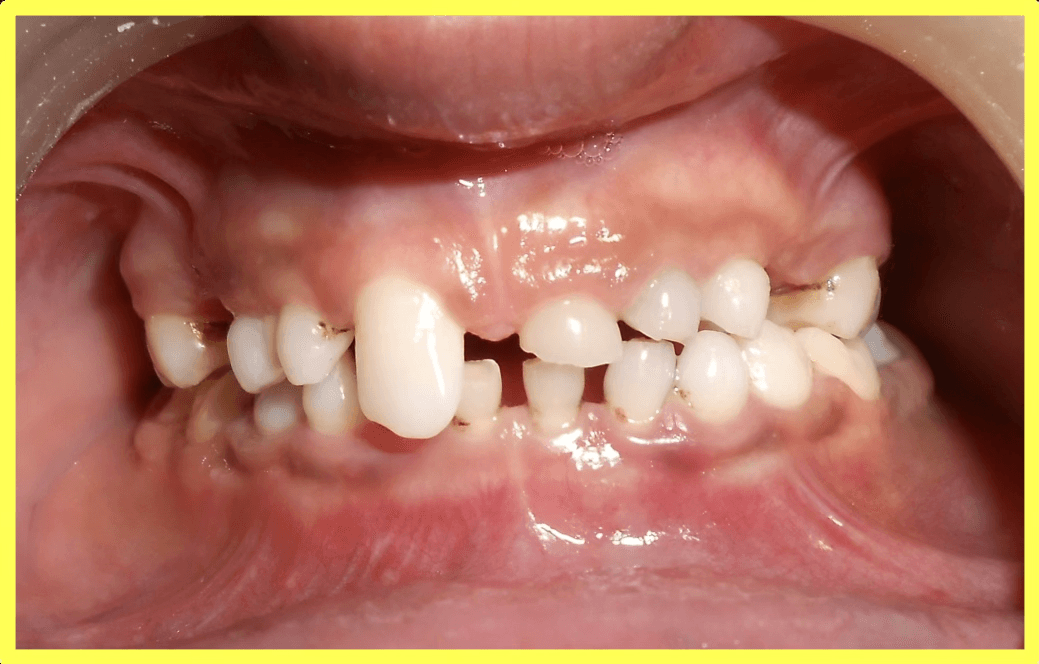

Initial condition

Missing permanent teeth and awkward smile

A 13-year-old male patient presented with oligodontia (congenitally missing permanent teeth) and retained deciduous (milk) teeth. Only two permanent lower molars were present. Treatment involved root canal therapy for all existing teeth followed by telescopic removable metallic PFM prosthesis for complete rehabilitation.

Comprehensive oral examination and OPG X-ray revealed oligodontia with only two permanent lower molars present. Patient had multiple retained deciduous teeth with aesthetic and functional concerns.